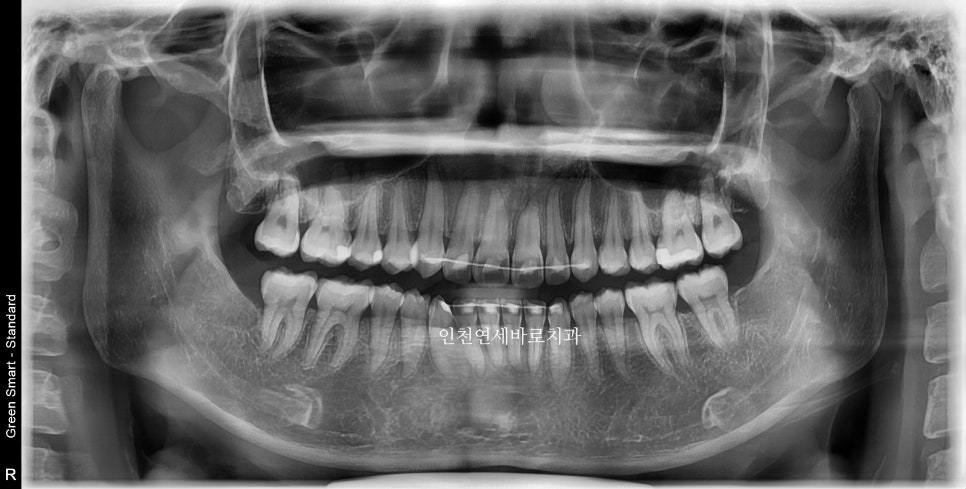

이 환자분은 14개의 장치가 끝난 후 한번의 재제작을 했습니다

위 사진이 7월에 재제작 했을 때 모습입니다.

2월초부터 장치를 착용했고 10월에 마무리 했습니다.

1개의 장치를 7일씩 착용하고, 중간에 재제작 한달이라는 기간이 포함된 기간입니다.

전후 비교입니다

전 후 교합의 비교입니다.

안정적으로 교합이 형성되었습니다